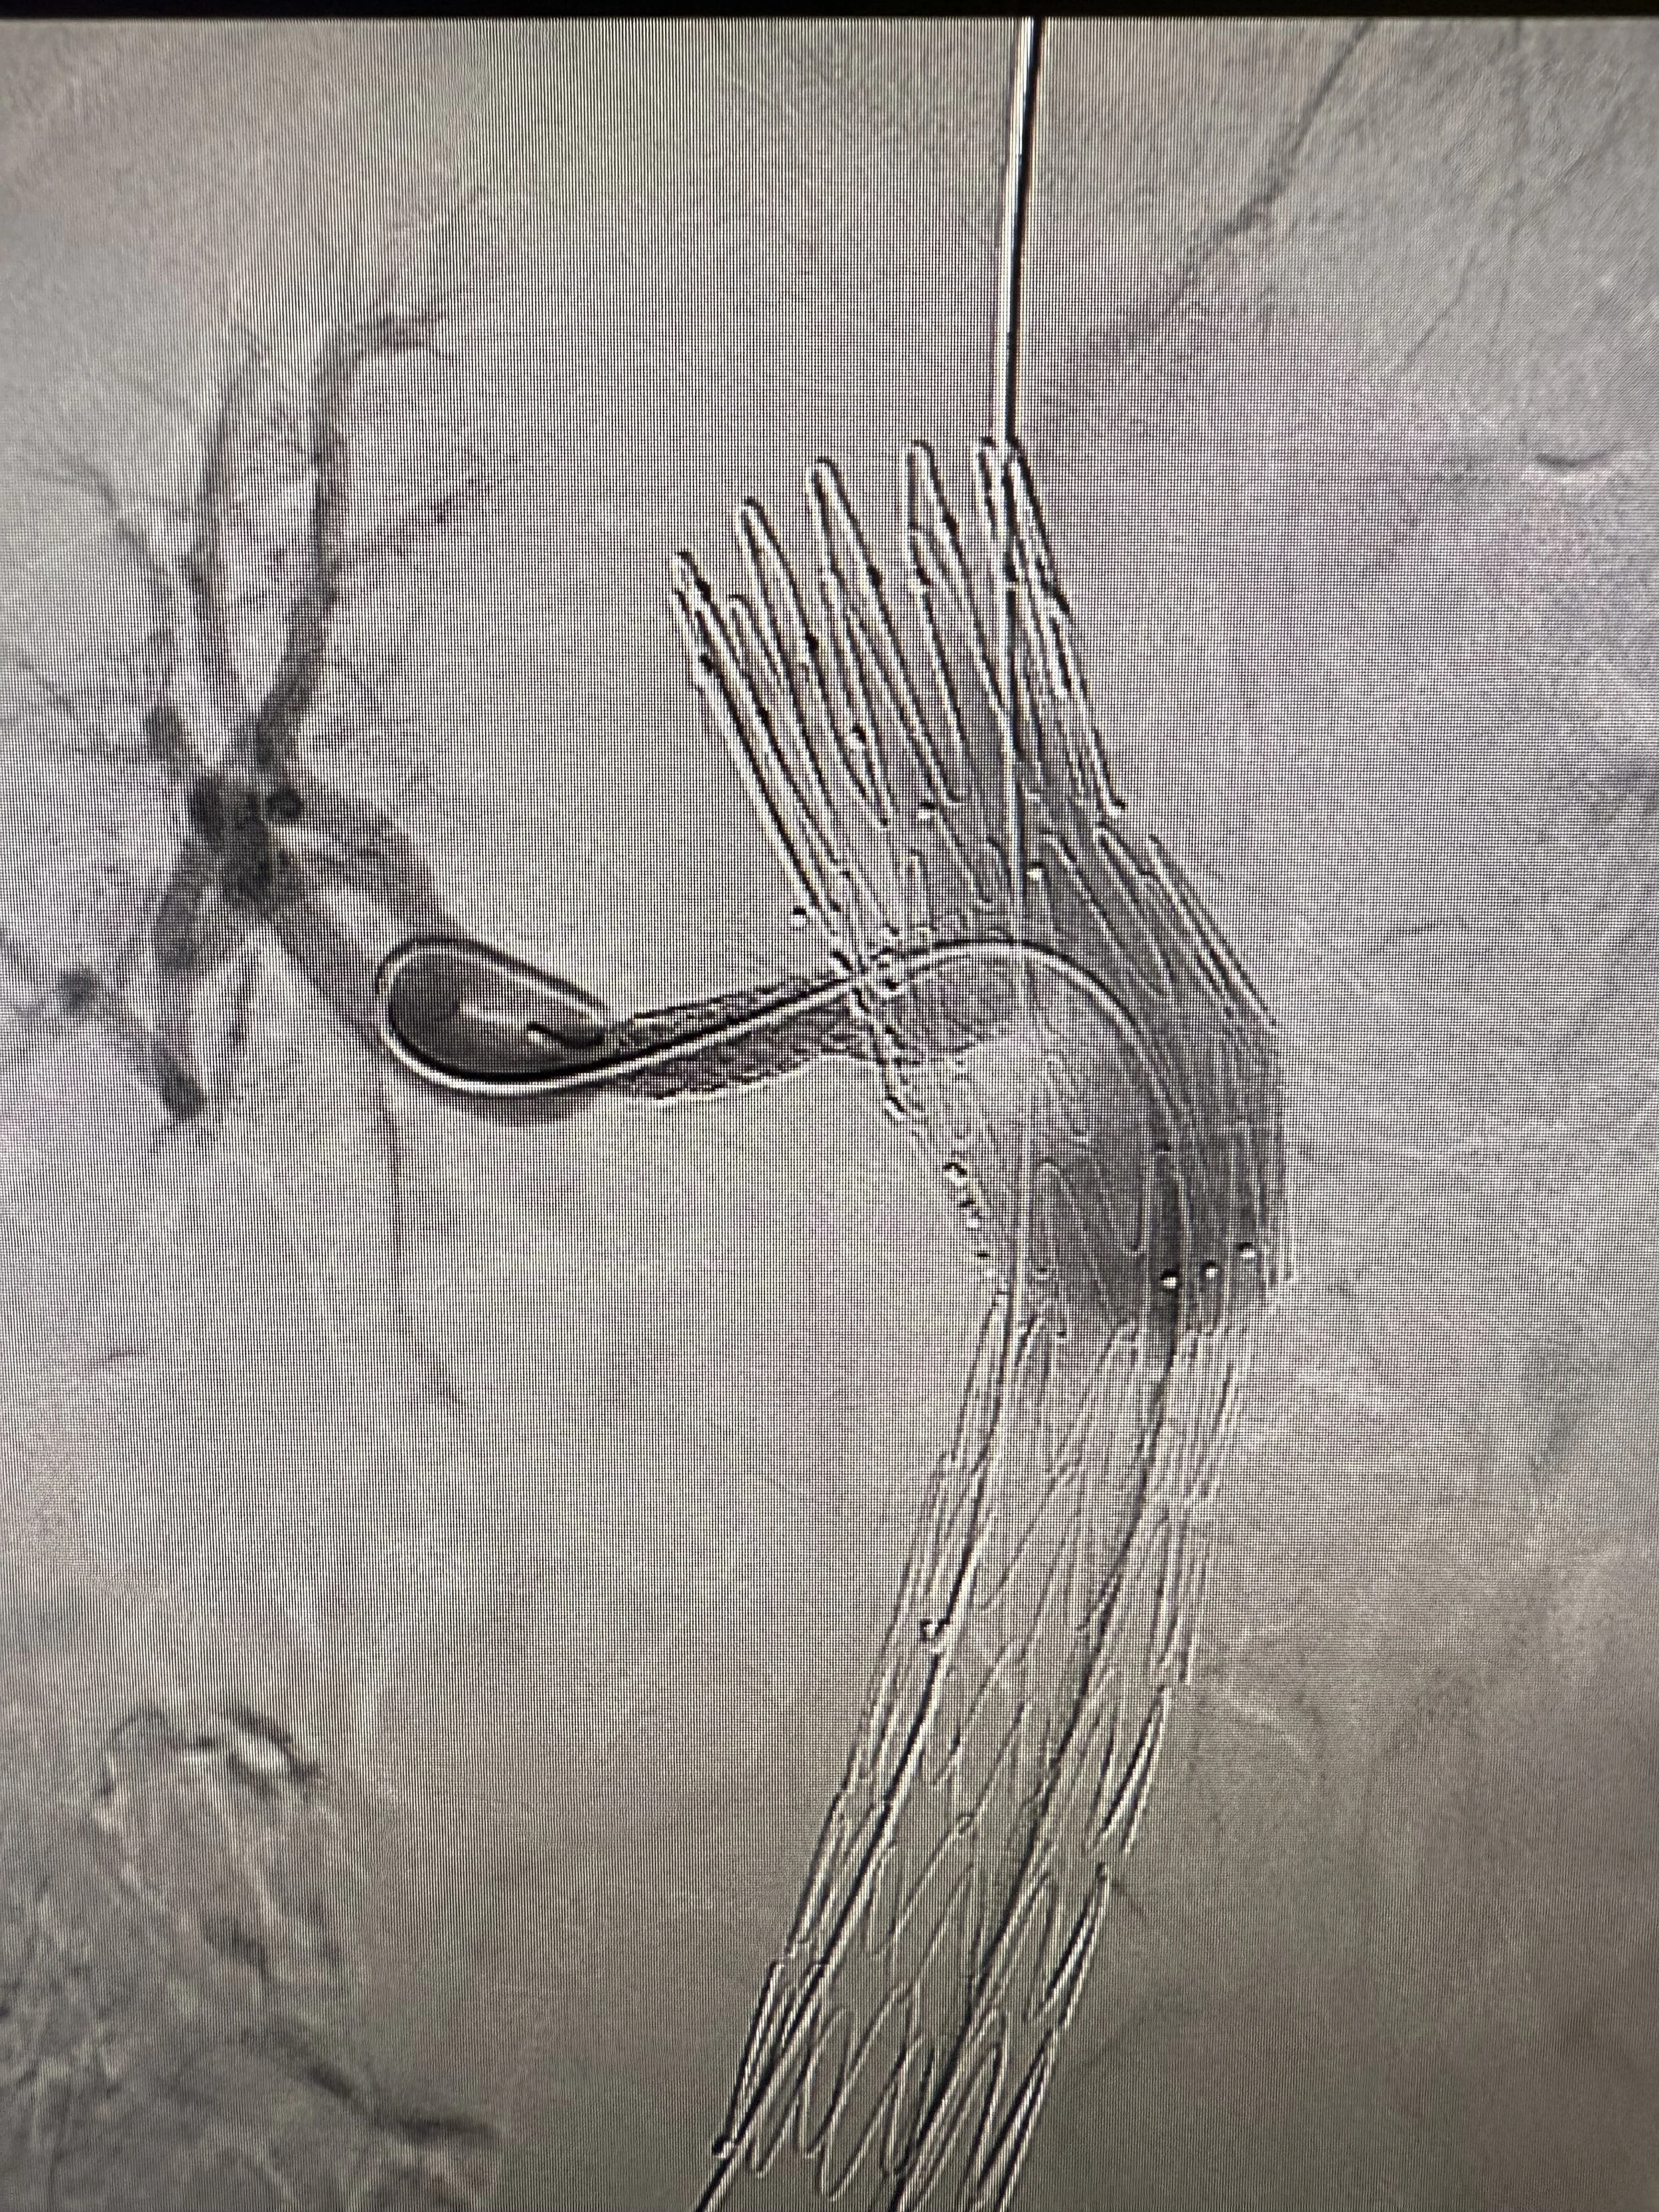

Visualisierung

Ich bin bekannt für meine chirurgischen Zeichnungen und Skizzen. Mit meinen Visualisierungen trage ich dazu bei, meinen Patient:innen komplexe medizinische Inhalte verständlich zu vermitteln – fachlich fundiert und mit Blick fürs Wesentliche.

chirurgische

Zeichnungen